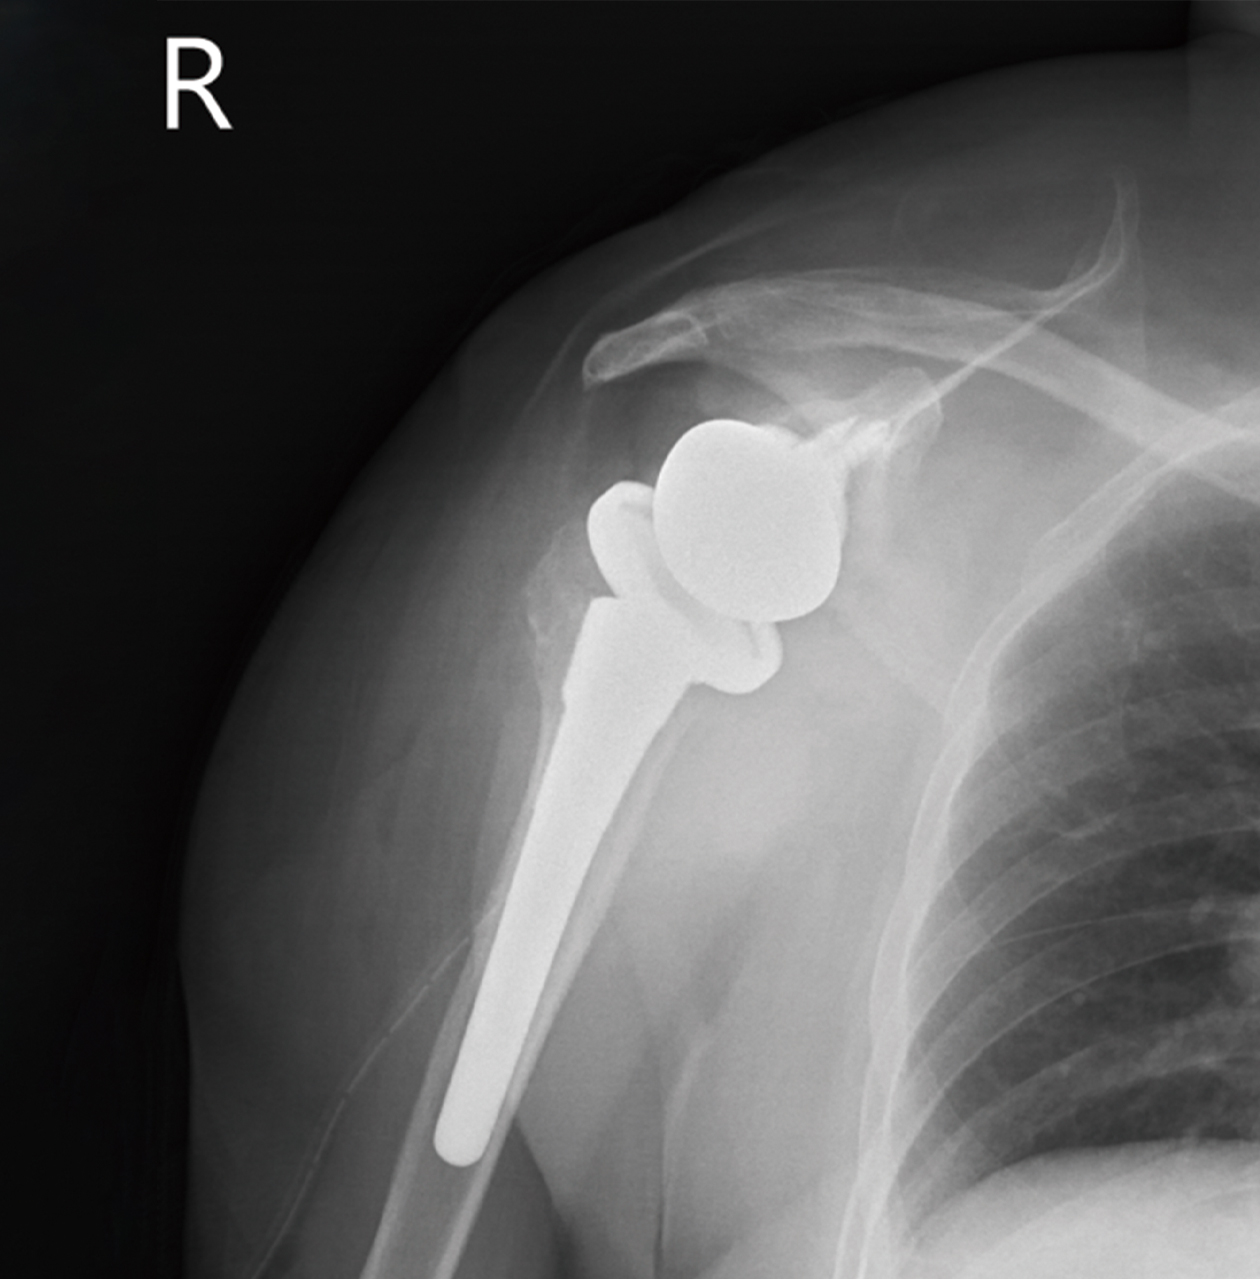

黃先生52歲,左肩疼痛多年,手無法上舉,一年來症狀加劇,經檢查發現肱骨頭缺血性壞死併肩關節炎,核磁共振發現大片全層旋轉肌破裂,接受了反置式人工全肩關節置換手術治療,並投入計劃性復健治療,目前疼痛消失,手已可上舉接近150度。

左側肱骨頭缺血性壞死續發關節炎併旋轉肌腱斷裂,經反置式人工全肩關節置換手術治療。